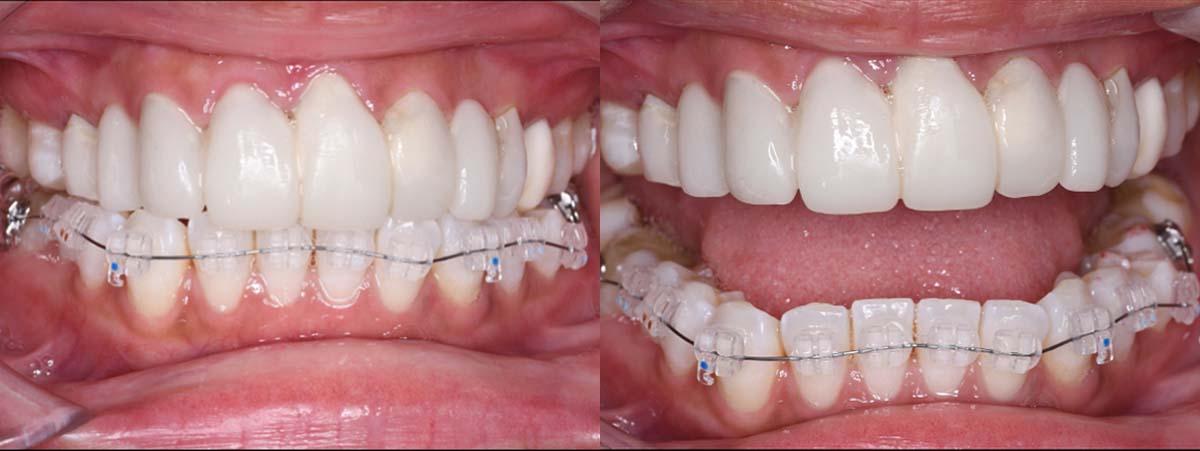

12月16日

12月23日

1月9日

1月30日

2月20日

3月13日

4月24日

9月25日